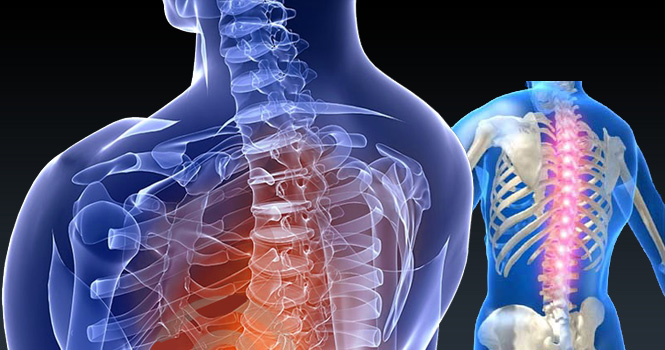

• Spine and Backache Management